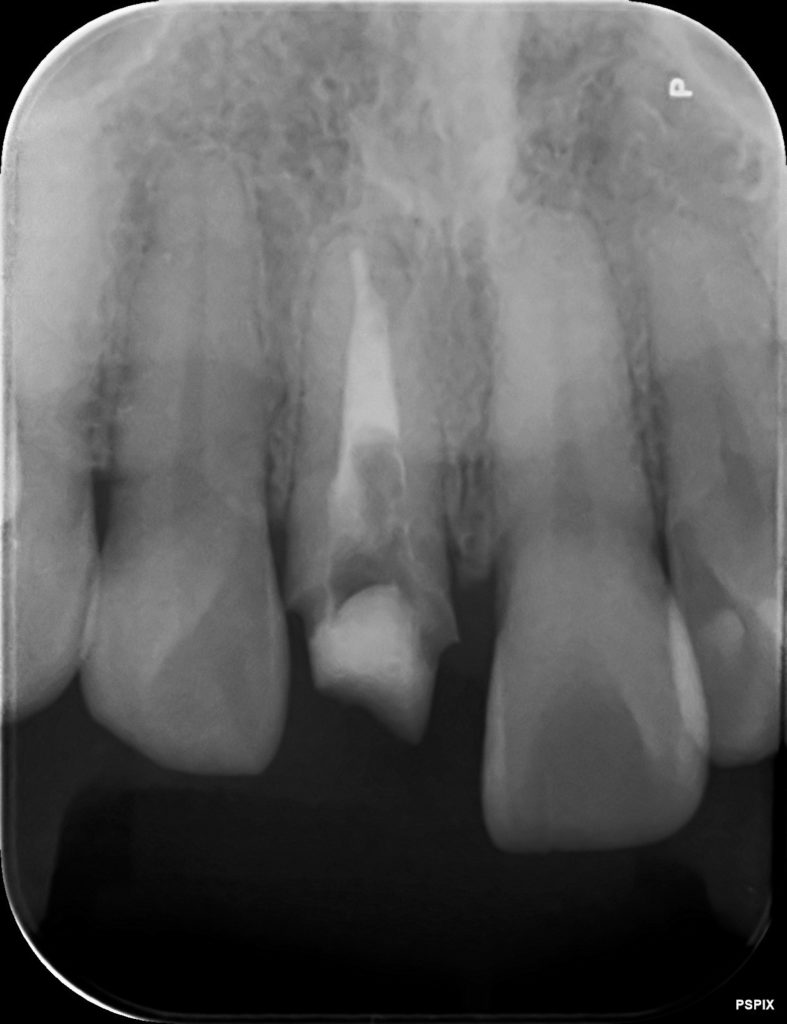

この黒い原因は、レントゲン写真を見ると分かります。

差し歯が埋め込まれています。

青い部分が白く写っており、メタルコアという金属の土台が埋め込まれています。

こちらの歯は神経がもう無いのですが、本来されていないといけない根管治療がされていません。

矢印の箇所ですが、神経のあった根管が黒く写っています。

本来は根管治療がしっかりされていると、材料が入るために白くレントゲン写真で写ります。